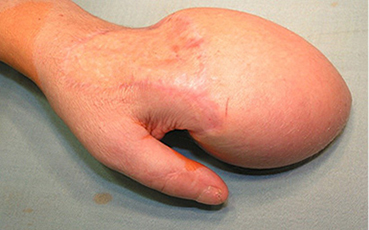

Į VšĮ Respublikinę Vilniaus universitetinę greitosios pagalbos ligoninę 2004 m. spalio mėn. pristatyta 43 m. moteris, patyrusi sunkią traumą – volais buvo nuplėšti kairės plaštakos minkštieji audiniai, per proksimalinius tarppirštakaulinius sąnarius amputuoti II ir V pirštai. Pacientė skubiai hospitalizuota į Plastinės ir rekonstrukcinės chirurgijos skyrių operacinio gydymo. Priimtas sprendimas minkštųjų audinių defektus padengti kirkšnies lopu.

1 pav.

2 pav.

Kairės plaštakos minkštųjų audinių Degloving amputacija. Nugarinis ir delninis paviršiai (1 ir 2 pav.)